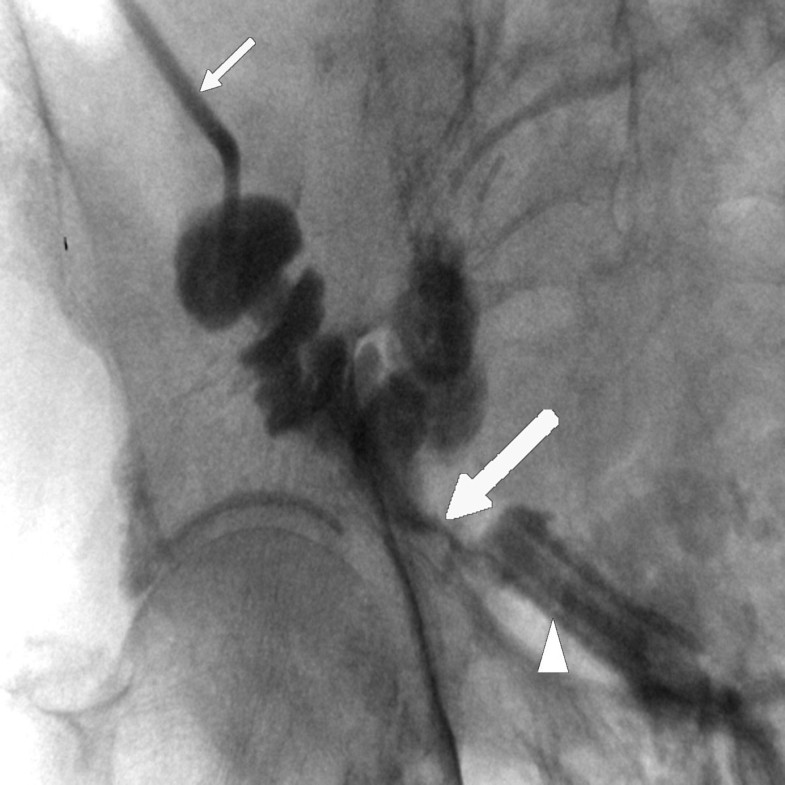

From www.ajronline.org

Percutaneous Treatment by Interventional Radiologists of Anastomotic Anastomotic Leak Bladder Icd 10 In this review we investigate and discuss all matters directly related to urethrovesical anastomotic leak, specifically how to diagnose. The purposes of this article are to illustrate the pattern of anastomotic leak after ralrp on ct cystography and to review key surgical techniques of ralrp to explain the mechanism of the intraperitoneal leak. (1) simple fistulas versus large sinuses; N99.89. Anastomotic Leak Bladder Icd 10.